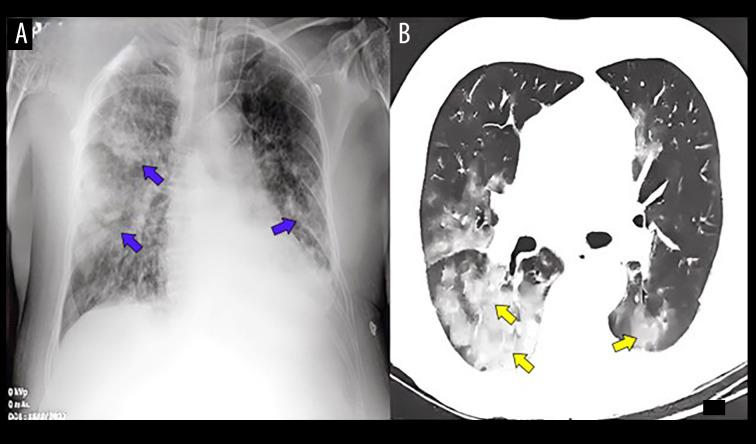

BACKGROUND Despite global vaccination efforts, COVID-19 still necessitates effective treatments for severe cases that can quickly escalate to life-threatening complications, such as acute respiratory distress syndrome (ARDS) and secondary pulmonary arterial hypertension (PAH). Here, we present the clinical journey of a 73-year-old Ecuadorian man who developed severe COVID-19 pneumonia complicated by an opportunistic Candida krusei infection and ARDS, subsequently progressing to long-term PAH, managed with bosentan, an endothelin 1 (ET-1) antagonist. CASE REPORT The patient, vaccinated with 2 doses of CoronaVac, experienced severe COVID-19 complications, including ARDS and secondary PAH, further complicated by a C. krusei infection. Despite prompt mechanical ventilation and intensive care, his condition rapidly deteriorated. Clinical evaluation confirmed COVID-19-associated ARDS, secondary PAH, and C. krusei infection through bronchoalveolar lavage. The therapeutic approach combined bosentan (125 mg twice daily) with dual antifungal therapy, leading to significant stabilization and eventual discharge. Post-discharge assessments showed persistent cardiopulmonary dysfunction, consistent with post-COVID-19 syndrome. CONCLUSIONS This case highlights critical COVID-19 complications in a vaccinated patient. While vaccination may provide substantial protection, COVID-19 pneumonia treated with corticosteroids can increase the risk of opportunistic infections like C. krusei, and ARDS can lead to pulmonary fibrosis and PAH. This case underscores the need for research on therapeutic strategies for complex COVID-19 cases and emphasizes comprehensive, personalized care for managing COVID-19 complications and sequelae.

该患者接种了2剂科兴疫苗,出现了严重的新冠肺炎并发症,包括ARDS和继发性PAH,并因克柔念珠菌感染而进一步复杂化。尽管迅速进行了机械通气和重症监护,但其病情仍迅速恶化。通过支气管肺泡灌洗进行的临床评估证实了新冠肺炎相关的ARDS、继发性PAH和克柔念珠菌感染。治疗方法是将波生坦(每日两次,每次125毫克)与双重抗真菌治疗相结合,从而实现了显著的病情稳定并最终出院。出院后的评估显示存在持续的心肺功能障碍,这与新冠肺炎后综合征相符。